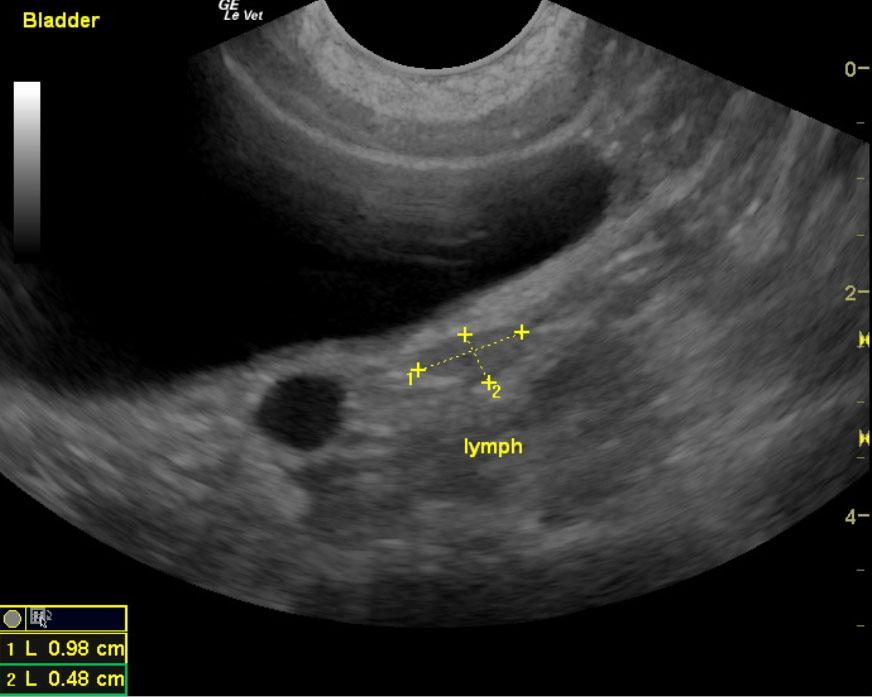

The kidneys in this patient had a persistent, slightly irregular contour, with the left kidney demonstrating slight pyelectasia (0.26 cm). The urinary bladder, trigone and pelvic urethra presented normal wall thicknesses with anechoic urine and normal tone. The urinary bladder revealed slight calculus at 0.23cm, yet was not shadowing. No evidence of inflammatory or neoplastic changes were noted.